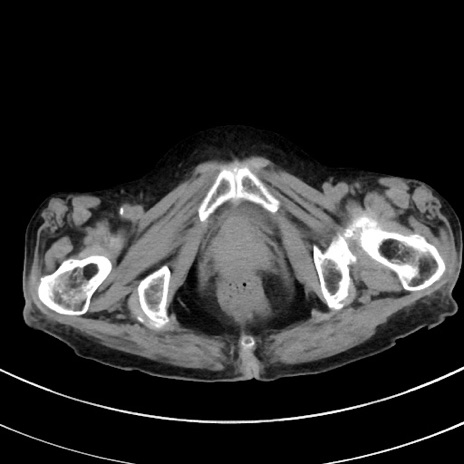

症例33(横断像)

【症例】70歳代 女性

【主訴】心窩部痛

【現病歴】延髄病変の精査・加療にて神経内科入院中。本日より心窩部痛あり。

【身体所見】右下腹部を中心に圧痛と反跳痛あり。

【データ】WBC 10900、CRP 0.02

冠状断像